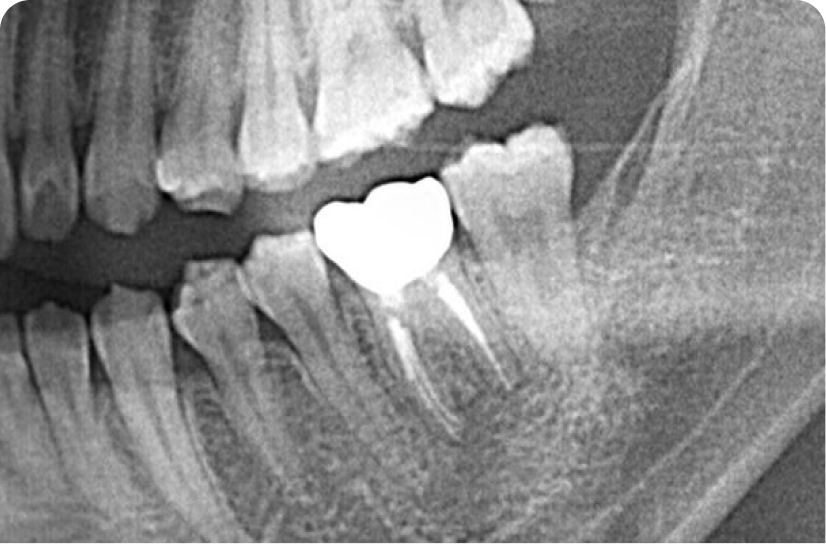

右下7自費根管治療をし残すことができた症例です。他院で抜歯と診断を受けても自費根管治療だと残すことができる場合があります。

左下6自費根菅治療の症例。